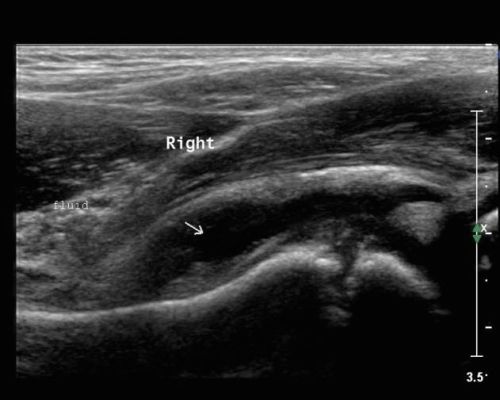

Παροδική Υμενίτιδα

Είναι η πιο συχνή αιτία επώδυνου ισχίου και χωλότητας σε παιδιά ηλικίας 6 με 10 ετών. Η πάθηση εμφανίζεται συνηθέστερα στα αγόρια με αναλογία 3 προς 1. Το κύριο σύμπτωμα είναι η χωλότητα στη βάδιση, ο περιορισμός των στροφικών κινήσεων του ισχίου καθώς και μερικές φορές η αντανάκλαση του πόνου στο ίδιο γόνατο.

Η θεραπεία που συνίσταται είναι η αποφόρτιση σκέλους - κλινοστατισμός και αυστηρή ξεκούραση για μερικές ημέρες.